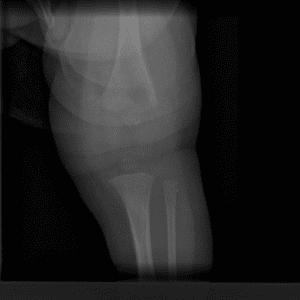

Pediatric Radiographs